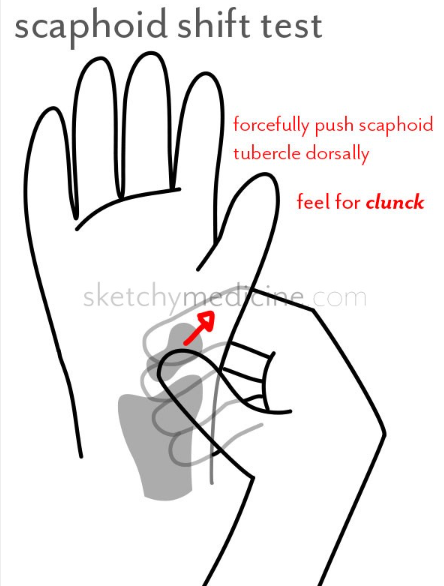

(5) 주상골 이동 검사(Scaphoid shift test)

-

- 주상골을 손등쪽으로 눌렀을때 부딪힘을 느끼기 위함입니다.